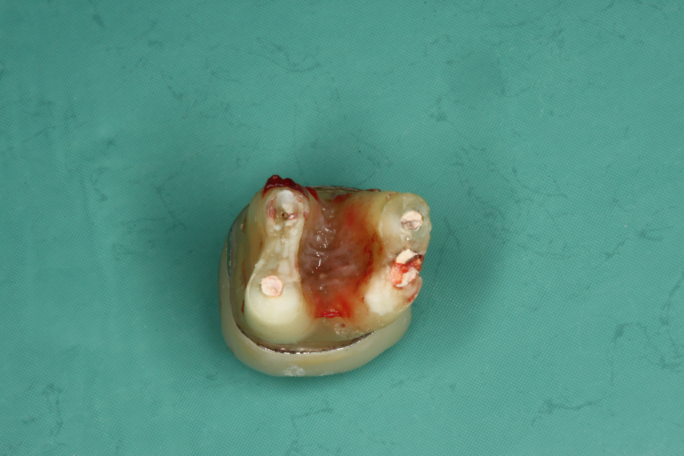

Wurzelkanalbehandelte Zähne sind tote Zähne! Auch die beste Mikro-Endodontie wird kaum eine komplett bakteriendicht abgeschlossene Wurzel realisieren können. Akzessorische Seitenkanäle und die Endo-Paro Verbindung über die Dentintubuli bleiben bestehen.

Pro Quadratmillimeter Wurzeldentin befinden sich 40 bis 60 tausend Dentinkanälchen, welche sich dann auf eine Länge von etwa 1 – 5 km summieren.

Dentinkanälchen sind 1 – 3 μm weit. Erreger (Bakterien, Pilze, Viren) haben eine Größe von 0,6 – 1 μm.

Makrophagen haben eine Größe von 5 – 20 μm.